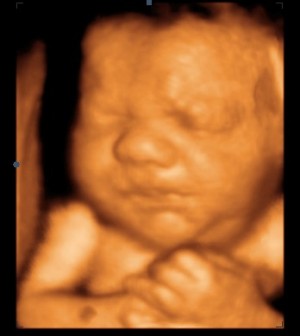

2. In stand 08.517 vind je Echowonder. Echowonder is een pretecho-bureau en maakt veel zwangeren blij met mooie beelden van hun kindje in 3D en 4D. In de webshop verkopen ze cadeaubonnen (heel handig!) en schitterende kristallen kubussen met de 3D echofoto van het kindje erin gelaserd. Heel bijzonder om te geven én om te krijgen.